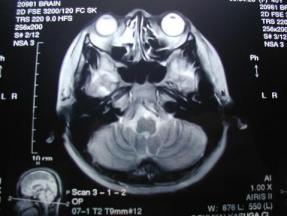

人間ドックだけでなく、体で重要な機能をつかさどる脳の検査も受けて、自覚症状のない病気の早期発見につとめましょう

脳ドックを受けてみた

脳ドック